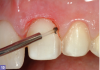

Single-cord technique.

Fig 8

The cord-packing technique is the most popular method of retraction and is done using a twisted, knitted, woven, or braided cord. A variety of natural and synthetic fiber types are used in making gingival retraction cords, including wool yarn, cotton, and silk. The cords are commercially available in plain versions and impregnated or pretreated with hemostatic medicaments. When using a cord-packing technique, an appropriately sized cord is gently placed into the gingival sulcus with the intent of mechanically displacing the soft tissues from the tooth and margin of the preparation. In general, it is best to use the smallest cord possible because larger cords can sometimes tear delicate gingival tissue, increase hemorrhage, and damage the sulcular epithelium. Fortunately, newer impression materials can capture excellent marginal detail within relatively small gingival spaces. Typically, retraction cords are placed after the tooth preparation is completed and then removed immediately before the impression tray is seated. Cords are packed with many different types of hand instruments.

Single-cord technique. The single-cord technique helps to deflect and manage the soft tissues. It works best with tooth preparations that terminate supragingival or at the tissue height.17Although occasionally uncomfortable for patients, the cord displaces the tissues, exposing the marginal area of the preparation, and remains in place until it is time for the final impression.17 The end of the cord packer must be thin enough to be placed in the gingival sulcus without damaging the tissue and causing any bleeding (Figure 8). The angulation of the instrument will help in the orientation for the placement.